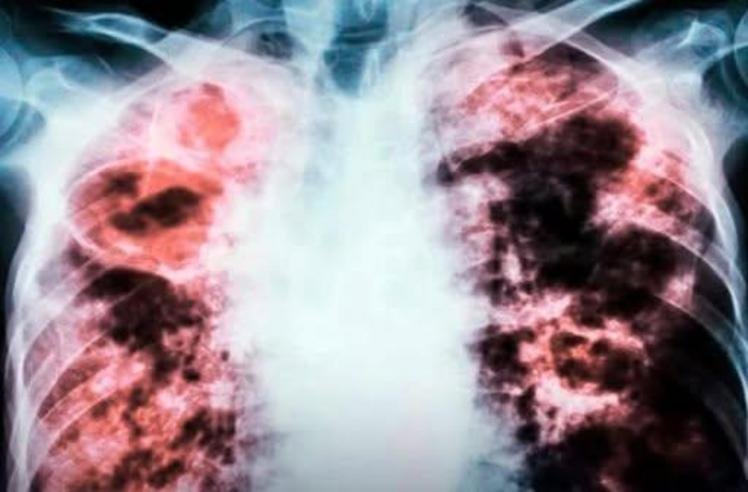

O pulmão é o motor da nossa respiração, um incansável trabalhador que, muitas vezes, é submetido a desafios silenciosos. Ameaças como o câncer de pulmão, uma condição que pode ser avassaladora, não se restringem apenas a fumantes, como muitos pensam. A qualidade do ar que respiramos, o ambiente em que vivemos, os alimentos que escolhemos e até mesmo a nossa herança genética desempenham papéis cruciais.

A saúde do seu pulmão é um tesouro que merece ser cuidado com dedicação. Esta “receita” vai muito além de uma lista de ingredientes e instruções; é um convite para uma jornada de escolhas conscientes, um compromisso diário com o seu bem-estar e a longevidade. O câncer de pulmão e outras doenças respiratórias podem ser ameaças silenciosas, mas a prevenção é uma voz poderosa que ressoa em cada decisão que você toma.